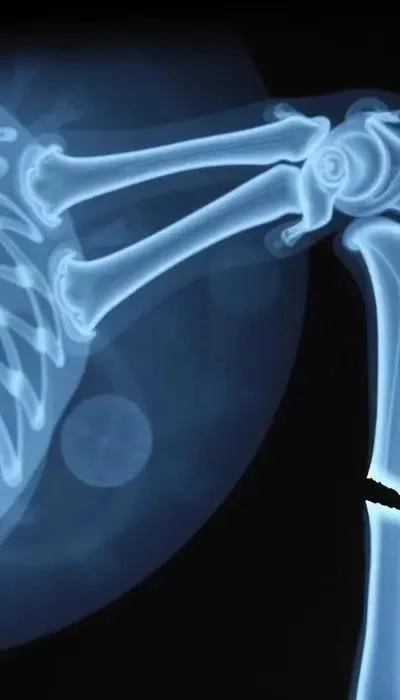

Диагностика перелома начинается с визуального осмотра и пальпации конечности. Ветеринарный врач может предположить наличие перелома, если животное не опирается на поврежденную лапу (как было отмечено 24 мая 2023 года). Однако для точного определения типа и локализации перелома необходимо рентгеновское исследование. В сложных случаях могут потребоваться дополнительные исследования, такие как компьютерная томография (КТ) или ультразвуковое исследование (УЗИ).

Лечение перелома может быть консервативным или хирургическим. Консервативное лечение включает наложение гипса, шины или повязки. Однако, как указывалось 22 ноября 2021 года, в некоторых случаях необходимо оперативное вмешательство – остеосинтез с установкой пластин и винтов. Выбор метода лечения зависит от типа перелома, его локализации и общего состояния животного. Медикаментозная поддержка, включающая обезболивающие, антибиотики и противовоспалительные препараты, играет важную роль в процессе лечения.